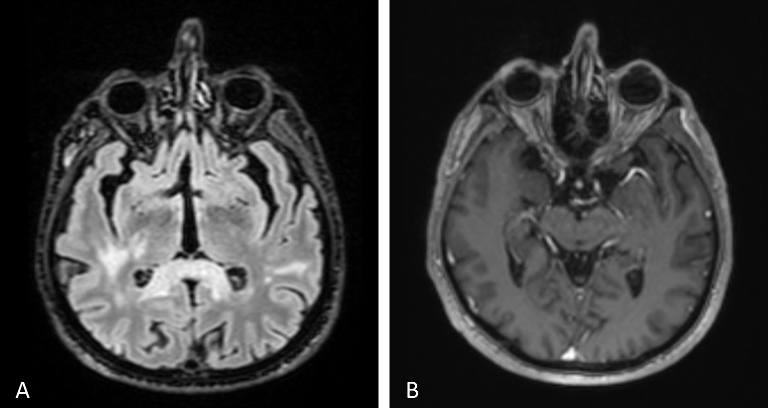

The systemic workup was suggestive of a granulomatous process, including lymphopenia, high CRP level, 2-fold increase in angiotensin-converting enzyme (ACE), purified protein derivative (PPD) anergic, Quantiferon+, and findings consistent with previous tuberculosis (TB) on thorax computed tomography (CT). However, multiple parenchymal nodular lesions were observed in cranial and orbital MR scans, along with thickening and enhancement of the left optic disc (Figure 1 [Fig. 1]). These findings are indicative of an infiltrative process, which corresponds to the patient’s systemic condition. The patient has experienced a 7–8 kg unintentional weight loss over the past few months, along with fatigue and a history of smoking 30 packs per year. We did not find any evidence of malignancy in the cerebrospinal fluid sample or vitreous aspirate.

Figure 1: Contrast and non-contrast cranial MRI sections from systemic investigation.

The left optic nerve appeared bulkier and larger, with multiple nodular lesions visible in the brain parenchyma (A–B). The choroidal and retinal layers were diffusely thickened and showed greater enhancement in the left eye compared to the right (B).